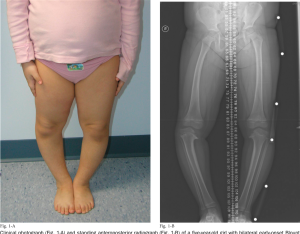

Blount disease adalah gangguan pertumbuhan pada tulang kering (tibia) bagian atas yang menyebabkan kaki anak tampak melengkung ke luar atau dikenal sebagai kaki O. Berbeda dengan kaki O normal pada bayi yang biasanya bisa membaik sendiri, Blount disease bersifat progresif, artinya kelengkungan bisa semakin parah jika tidak ditangani sejak dini.

Kondisi ini bisa terjadi pada balita maupun anak yang lebih besar dan remaja. Masalah utamanya adalah pertumbuhan tulang di sisi dalam tibia yang tidak optimal, sehingga posisi kaki menjadi tidak lurus.

Pada banyak bayi, kaki O adalah bagian dari proses tumbuh kembang dan biasanya akan membaik seiring waktu. Namun, jika setelah usia sekitar 2–3 tahun kaki anak justru semakin melengkung, terlihat tidak simetris, atau tidak menunjukkan perbaikan, kondisi ini perlu diwaspadai sebagai kemungkinan Blount disease.

Perbedaan utamanya, kaki O normal cenderung membaik sendiri, sedangkan pada Blount disease kelengkungan justru bertambah.